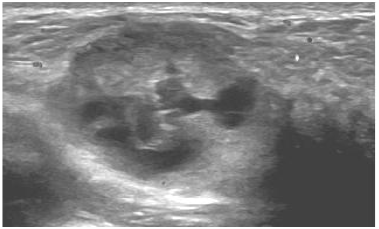

Paciente puérpera com 33 anos, informa que há duas semanas, durante amamentação, palpou um nódulo na mama direita.

O achado encontrado no exame de imagem classifica-se como: